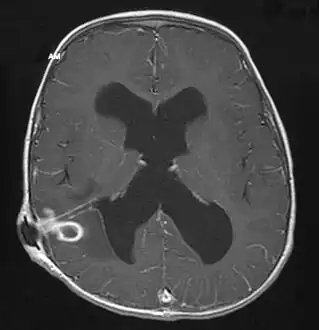

| Brain abscess in a person with a CSF shunt.[1] | |

MRI (T1 with contrast) showing the ring-enhancing lesion. From a rare case report of an abscess formed as a complication of the CSF shunt. Jamjoom et al., 2009.[1]